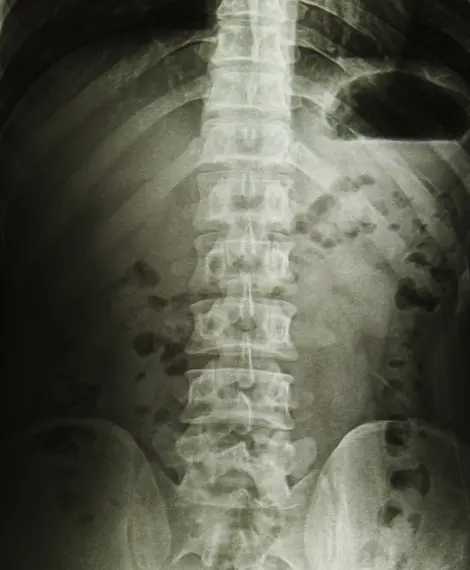

A infiltração guiada por ultrassom na coluna é um procedimento minimamente invasivo em que medicamentos anti-inflamatórios (corticoides) e anestésicos são injetados em estruturas específicas da coluna vertebral com auxílio de ultrassonografia em tempo real. Diferente da infiltração guiada por fluoroscopia, o ultrassom não utiliza radiação ionizante, tornando o procedimento mais seguro e acessível.

Em Goiânia, o Dr. Aurélio Arantes realiza infiltrações guiadas por ultrassom para tratamento de dor lombar, dor cervical, síndrome facetária, dor ciática e outras condições dolorosas da coluna. O ultrassom permite visualizar a agulha, os tecidos moles, vasos sanguíneos e nervos durante toda a aplicação, garantindo precisão e reduzindo riscos.